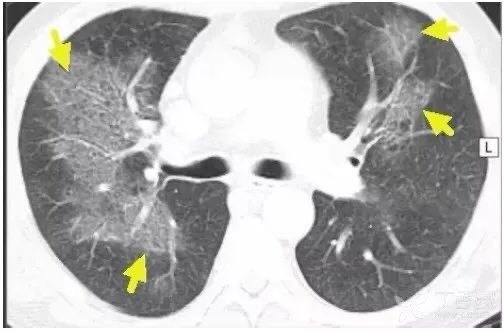

反晕征

顾名思义,表现与晕征相反,是一种外带密度略高(白箭)于内部磨玻璃密度区(蓝箭)的 CT 表现。一般常见于肺结核和真菌肺炎。